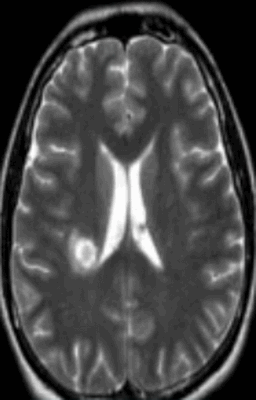

Очаг демиелинизации на МРТ

Обычно очаги демиелинизации выглядят как множественные мелкие участки гиперинтенсивного МР-сигнала, расположенные в одном или нескольких отделах головного мозга. По степени их распространенности, давности и одновременности возникновения врач судит о масштабах развития заболевания.

Очаги демиелинизации

Некоторые заболевания нервной системы сопровождаются повреждением глиальной оболочки длинных отростков нейронов. В результате патологических изменений нарушается проведение импульсов. Подобное состояние сопровождается неврологической симптоматикой различной степени интенсивности. Демиелинизация нервных волокон может быть вызвана: